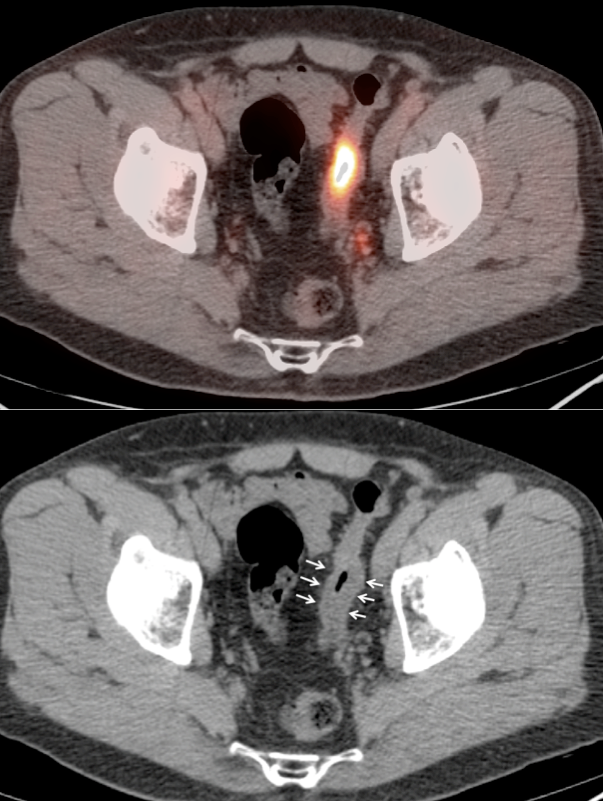

• Hemorrhoids are often intensely avid in the ano-rectal region (and are usually not visible on the CT images). Be certain that uptake does not lie more superiorly in the rectum. Additionally, carefully assess for an accompanying soft tissue density to exclude an anal cancer.

• Beware the small rectal cancer!  As the ano-rectal region frequently demonstrates intense physiologic uptake, it is very easy to overlook a rectal malignancy, especially if it is an incidental finding.  To avoid this error, always evaluate the rectum carefully on the sagittal whole body images.  It is shocking to see how readily apparent a rectal cancer can be on these images, yet so easily overlooked in the axial plane.